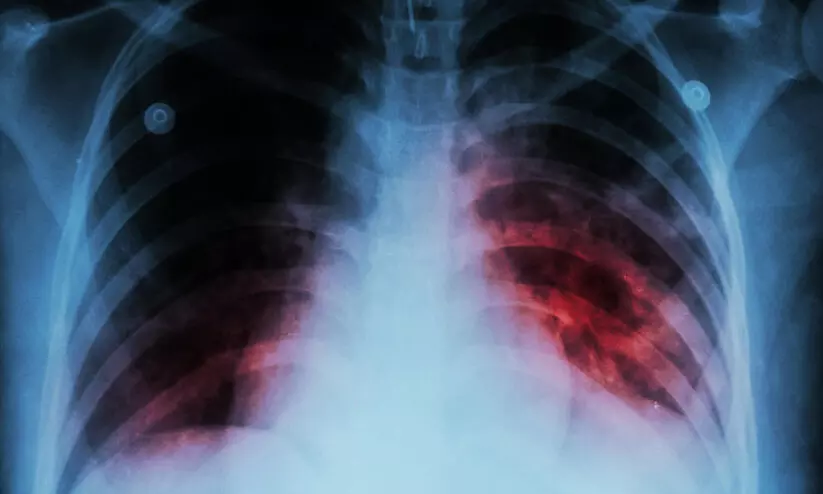

text_fieldsതൃശൂര്: ജില്ലയില് 2157 ആളുകള്ക്ക് ക്ഷയരോഗം ബാധിച്ചതായി ആരോഗ്യവകുപ്പിന്റെ കണക്ക്. ഇവരില് 1419 ആളുകള് പുരുഷന്മാരും 738 പേര് സ്ത്രീകളും 54 പേര് കുട്ടികളുമാണ്. കൂടാതെ 157 മരണവും റിപ്പോര്ട്ട് ചെയ്തു. ശ്വാസകോശ ക്ഷയരോഗം ബാധിച്ചവരായി 1148ഉം, ശ്വാസകോശേതര ക്ഷയരോഗം 738 പേര്ക്കുമാണ് ബാധിച്ചത്.

രോഗം ബാധിച്ചവരില് കൂടുതലും മധ്യവയസിന് മുകളിലുള്ളവരാണെന്ന് ജില്ല ടി.ബി. ഓഫിസര് ഡോ. അജയ് രാജന് വാര്ത്തസമ്മേളനത്തില് പറഞ്ഞു. സംസ്ഥാനത്ത് 21799 പേരാണ് ക്ഷയരോഗബാധിതർ. 1959 മരണങ്ങളാണ് രോഗം മൂലം റിപ്പോര്ട്ട് ചെയ്യപ്പെട്ടത്. രാജ്യത്തെ ക്ഷയരോഗ ബാധിതര് 28 ലക്ഷമാണെന്നും കണക്കുകള് പറയുന്നു. 3,15,000 പേര് ക്ഷയരോഗം ബാധിച്ച് മരിച്ചിട്ടുണ്ട്. ശ്വാസകോശ ക്ഷയമാണ് ഏറ്റവുമധികം റിപ്പോര്ട്ട് ചെയ്യുന്നത്.